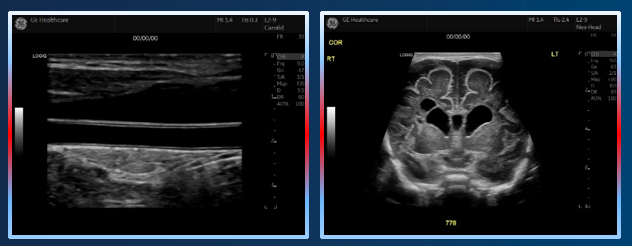

冰晶探头技术带来高穿透力——兼顾穿透及分辨。

超宽频宽相应,频带:2-10MHz——兼容血管、小器官、腹部、小儿全身应用。

支持B-Flow灰阶血流成像及MVI超微细血流成像。

支持双模态弹性成像、双模态超声造影、容积导航。

穿透力与分辨力的完美体现